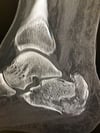

Перелом пяточной кости

На этой рентгенограмме виден оскольчатый перелом пяточной кости.

Image courtesy of Danielle Campagne, MD.